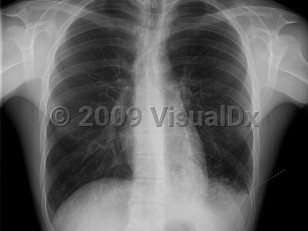

Influenza presents with classic flu-like illness consisting of the sudden onset of fever, malaise, sore throat, nonproductive cough, myalgias, headache, and nasal congestion. Chills are common, as are nausea and vomiting in children. After 48 hours, cough may increase and produce sputum. There may be associated dyspnea and/or mild-to-moderate pleuritic chest pain. Upon physical examination, unilateral or bilateral inspiratory rales may be appreciated or diminished breath sounds. Pregnant individuals are at increased risk for severe illness from influenza.

Primary viral pneumonia is the complication responsible for the most influenza-related deaths. Those with pre-existing cardiopulmonary disease or who are pregnant are at the greatest risk. The initial clinical presentation is the same, but dyspnea increases in severity. Productive cough may be blood tinged. Massive hemoptysis has been reported. When severe, there may be profound respiratory distress with tachypnea, tachycardia, and cyanosis. Rales and wheezes will spread throughout the chest from the lower lung.